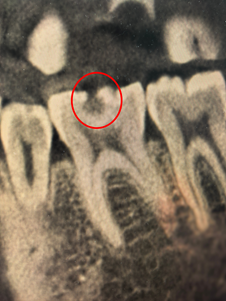

近日,杭州的李女士(化名)捂着半边脸来到杭州师范大学附属医院口腔医学中心,经检查,牙体牙髓专科负责人陈幸副主任医师发现她的牙齿已有深龋洞波及牙神经,必须做根管治疗。

无糖碳酸饮料里的酸,会直接酸蚀牙釉质导致“牙齿脱矿”,破坏力不输糖;果干黏稠、糖分高,特别容易粘在牙齿缝隙里,成了细菌滋生的温床。这些“隐形酸”与“隐形糖”悄然损害牙齿,待出现冷热刺激痛时,龋坏往往已深达牙齿内部。

接近牙神经的龋洞